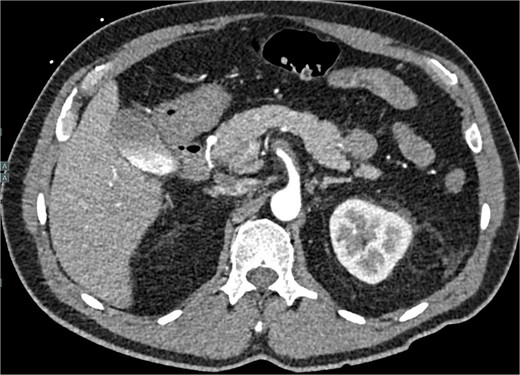

The patient was initially managed conservatively with blood pressure control and anticoagulation using Apixaban and aspirin. However, after one day of treatment, he experienced worsening abdominal pain and a hypertensive crisis with blood pressure reaching 228/113 mmHg. A follow-up CTA showed an extension of the SMA dissection extending into branch vessels, now associated with a small 1 cm aneurysm and hemoperitoneum (Fig. 2). Apixaban was stopped, and the patient was transitioned to a heparin drip, with an esmolol drip as needed for blood pressure control. As his symptoms improved, he was bridged back to apixaban and discharged on enoxaparin.

CTA demonstrating a more extensive SMA dissection extending into branch vessels. New hemoperitoneum most pronounced in the left abdomen with no active extravasation noted but probably arises from the left mesentery.